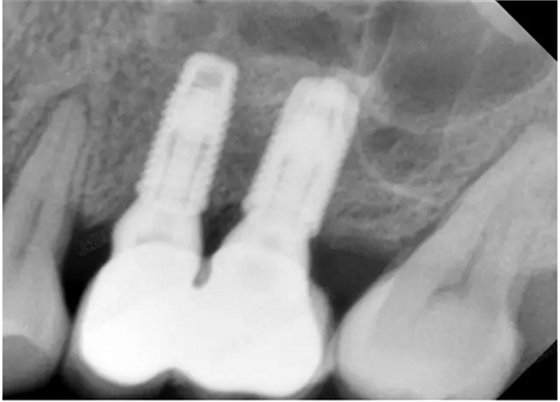

修復(fù)時(shí)根尖片

08.png